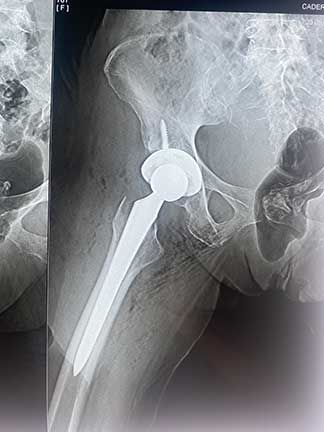

Prótesis de cadera

Es también conocida como reemplazo de cadera, la cual consiste en la sustitución de la articulación dañada o un implante de metal, cerámica o plástico que realiza la función de la articulación, mejorando el dolor.

¿Por qué se realiza?

Las indicaciones más comunes son la artrosis o desgaste de cadera en adultos mayores, otras indicaciones son las fracturas de cadera, el daño crónico o infección, artritis reumatoide, secuelas de enfermedades de la cadera o traumatismos, las cuales se presentan en adultos jóvenes y adultos mayores.